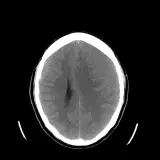

Over 2,100 interactive radiology cases, curated by radiologists for your level of training. Scroll, window, and view cases full screen — just like on PACS. Click linked findings in each writeup to jump straight to them on the image. Cases include sample reports, a focused discussion section, original illustrations, and videos.

完全交互式病例,配备您在 PACS 上期待的各项工具——滚动、调窗、缩放、平移、测量、ROI 和全屏模式。

丰富的标注直接在病例图像上突出关键发现。点击病例讲解中的关联发现,即可跳转至其在扫描上的精确位置。